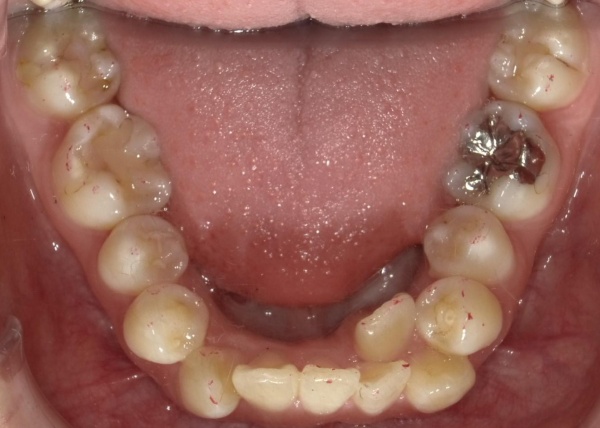

20代女性 マルチブラケット装置とアンカースクリューを併用してガタガタの歯並びや噛み合わせを改善した症例

治療前

ご相談内容 「前歯がガタガタしているのを治したい。噛み合わせが悪いのも気になる」とご相談いただきました。

カウンセリング・診断結果 拝見したところ、歯が生え揃うスペースが不足しているため、上下の前歯がガタガタに生える「叢生(そうせい)」でした。

骨格的な原因により、上の歯並びに対して下の歯並びが前方にずれて噛み合う「骨格性3級」だけでなく、上左右の側切歯は下の前歯の内側に噛み合っており、噛み合わせが反対になる「クロスバイト」の状態です。

また噛み合わせたときに、上下前歯の中心「正中」が顔の真ん中に位置するのが一般的ですが、患者様の場合、下前歯の中心が上顎の正中に対して左側に歯1本分ほどずれていました。

このまま放置すると、見た目が悪いだけでなく、噛み合わせに問題が出る、歯ブラシが当てにくいことで虫歯や歯周病のリスクも高まるといった可能性があります。

以上のことから、歯並びと噛み合わせを改善する治療が必要と診断しました。